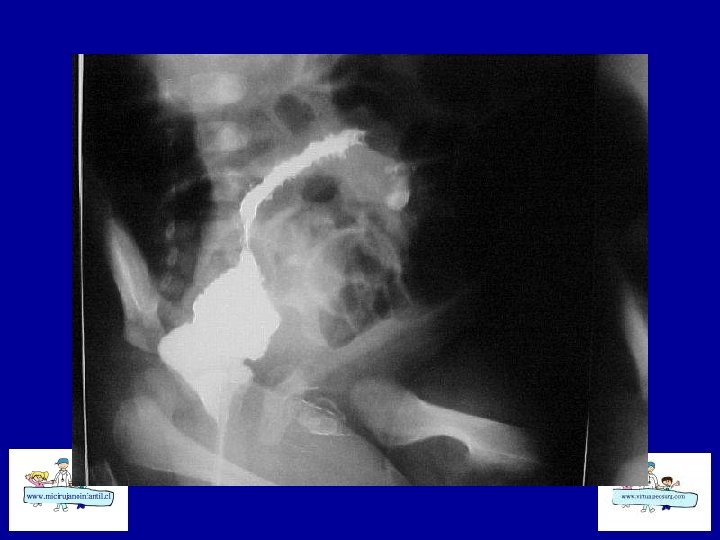

ECN-RADIOLOGÍA SIMPLE • • Distensión de asas Pneumatosis intestinal Asa fija (centinela) Gas Porta Edema de pared Ascitis Aire libre

ECN- CLASIFICACION (Bell) Etapa I: sospecha a CEG, sepsis inicial, Rx. distensión de asas moderada Etapa II: confirmada Ileo, sepsis más intensa , Rx: Ileo – pneumatosis b Hematoquezia Celulitis de pared, masa, grave, Rx: ascitis, gas porta Etapa III: grave Muy grave, CID, peritonitis Rx: ascitis Rx : pneumope ritoneo